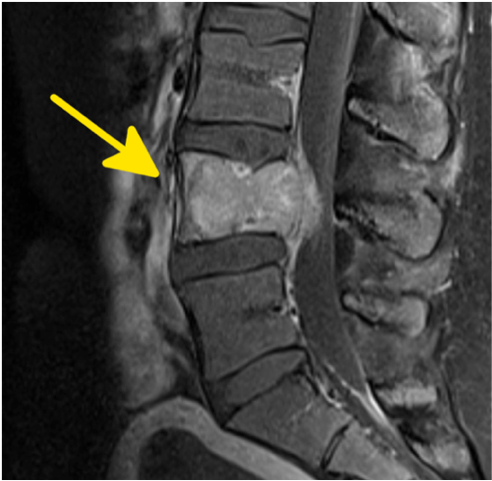

Tumore der Wirbelsäule gehören allgemein eher zu den Kontraindikationen für Physiotherapie insbesondere bei mechanischen Therapieformen wie Manuelle Therapie. In der Literatur wird deren Erscheinungsbild eher allgemein und zusammenfassend dargestellt. Es wird selten zwischen den einzelnen Formen in Lokalisation, Symptomatik und die Bedeutung für die Therapierbarkeit durch Physiotherapie unterschieden. Dieser Workshop bringt hier mehr Sicherheit

- Alle bekannten Formen von Tumoren an der Wirbelsäule und dem Rückenmark werden vorgestellt.

- Die Eigenschaften dieser Tumore (Ätiologie, Pathogenese, Symptomatik und Therapiemöglichkeiten) werden erörtert.